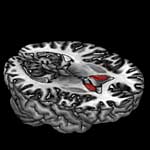

Bildunterschrift: Die Insulinempfindlichkeit im Nukleus caudatus hängt von Veränderungen im FTO-Gen und im Dopamin-D2-Rezeptor-Gen ab.

Bildquelle: Helmholtz Zentrum München an der Eberhard-Karls-Universität Tübingen (IDM)

"Unsere Untersuchungen zeigen, dass es Effekte hat, wenn beide Gene mutiert sind. Gibt es aufgrund des ANKK1-Polymorphismus weniger Dopamin-D2-Rezeptoren, haben Betroffene mit verändertem FTO einen höheren Körperfett-Anteil, größeren Bauchumfang sowie eine geringe Empfindlichkeit gegen Insulin im Körper. Zudem konnte auch in einer für den Dopamin-Stoffwechsel wichtigen Region des Gehirns, dem Nukleus caudatus, eine veränderte Insulin-Empfindlichkeit festgestellt werden?, fasst Heni die Ergebnisse zusammen. "Daraus schließen wir, dass die Auswirkungen eines veränderten FTO-Gens von der Anzahl der Dopamin-D2-Rezeptoren abhängt", ergänzt sein IDM-Kollege Prof. Dr. Hubert Preissl. Ist ein Betroffener Träger beider Mutationen, erhöht sich sein Risiko an Adipositas und Diabetes zu erkranken. "Leider liegt diese ungünstige Kombination beider Genveränderungen bei etwa einem Fünftel der Bevölkerung vor", sagt Heni.